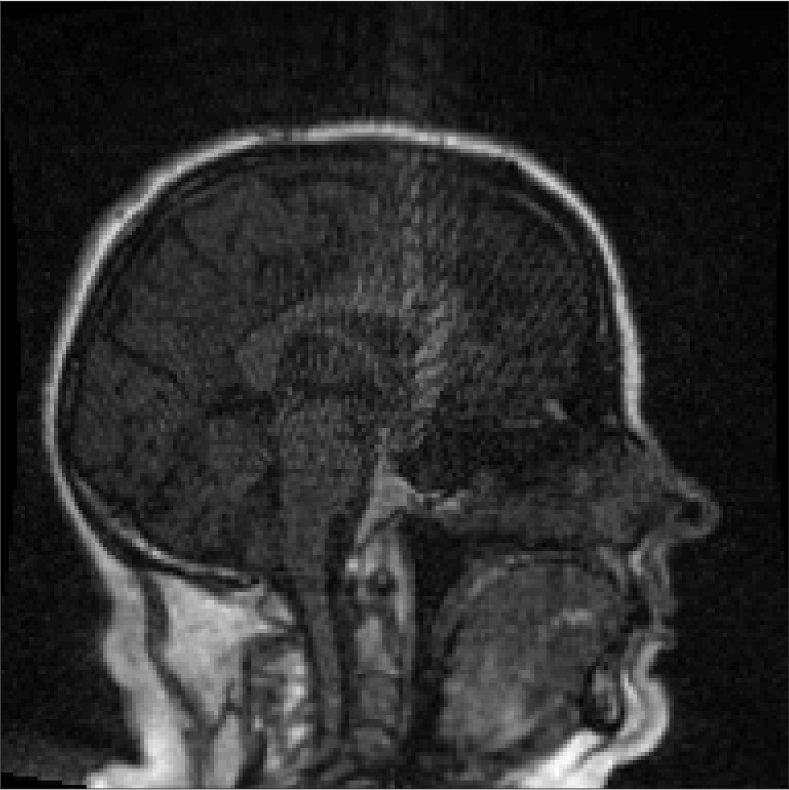

All MR images were acquired with a 1.5 T Siemens Espree scanner. The UTE images were reconstructed to 192×192×192192192192192\times 192\times 192 voxel bitmapped images with an isotropic resolution and a voxel size of 1.33 mm. The UTE sequences sampled the k-space radially with 30 000 radial spokes. CT images were acquired with a tube voltage of between 120 kV and 130 kV on either a GE Lightspeed Plus, Siemens Emotion 6 or GE Discovery 690. The in-plane pixel size varied between 0.48 mm to 1.36 mm and the slice thickness between 2.5 mm and 3.75 mm. Images of the same patient were co-registered and resampled to achieve voxel-wise correspondence between all five modes. A binary mask excluding most of the air surrounding the head was computed from the images and used to remove unnecessary data. Furthermore, to reduce the execution time of the parameter estimation phase, only 11 slices in the middle of the head of each patient was used during the parameter estimation phase, but all slices were used during the prediction phase (s-CT generation). Additional details concerning the data can be found in Johansson et al. [16]. Data from one slice of a patient is shown in Figure 3.

Refer to caption

(a) Binary mask

(b) CT

(c) First echo, 10superscript1010^{\circ}

(d) Second echo, 10superscript1010^{\circ}

(e) First echo, 30superscript3030^{\circ}

(f) Second echo, 30superscript3030^{\circ}

Figure 3: Binary data mask (panel a), CT image (panel b), The four MRI UTE sequences (panels c-f).